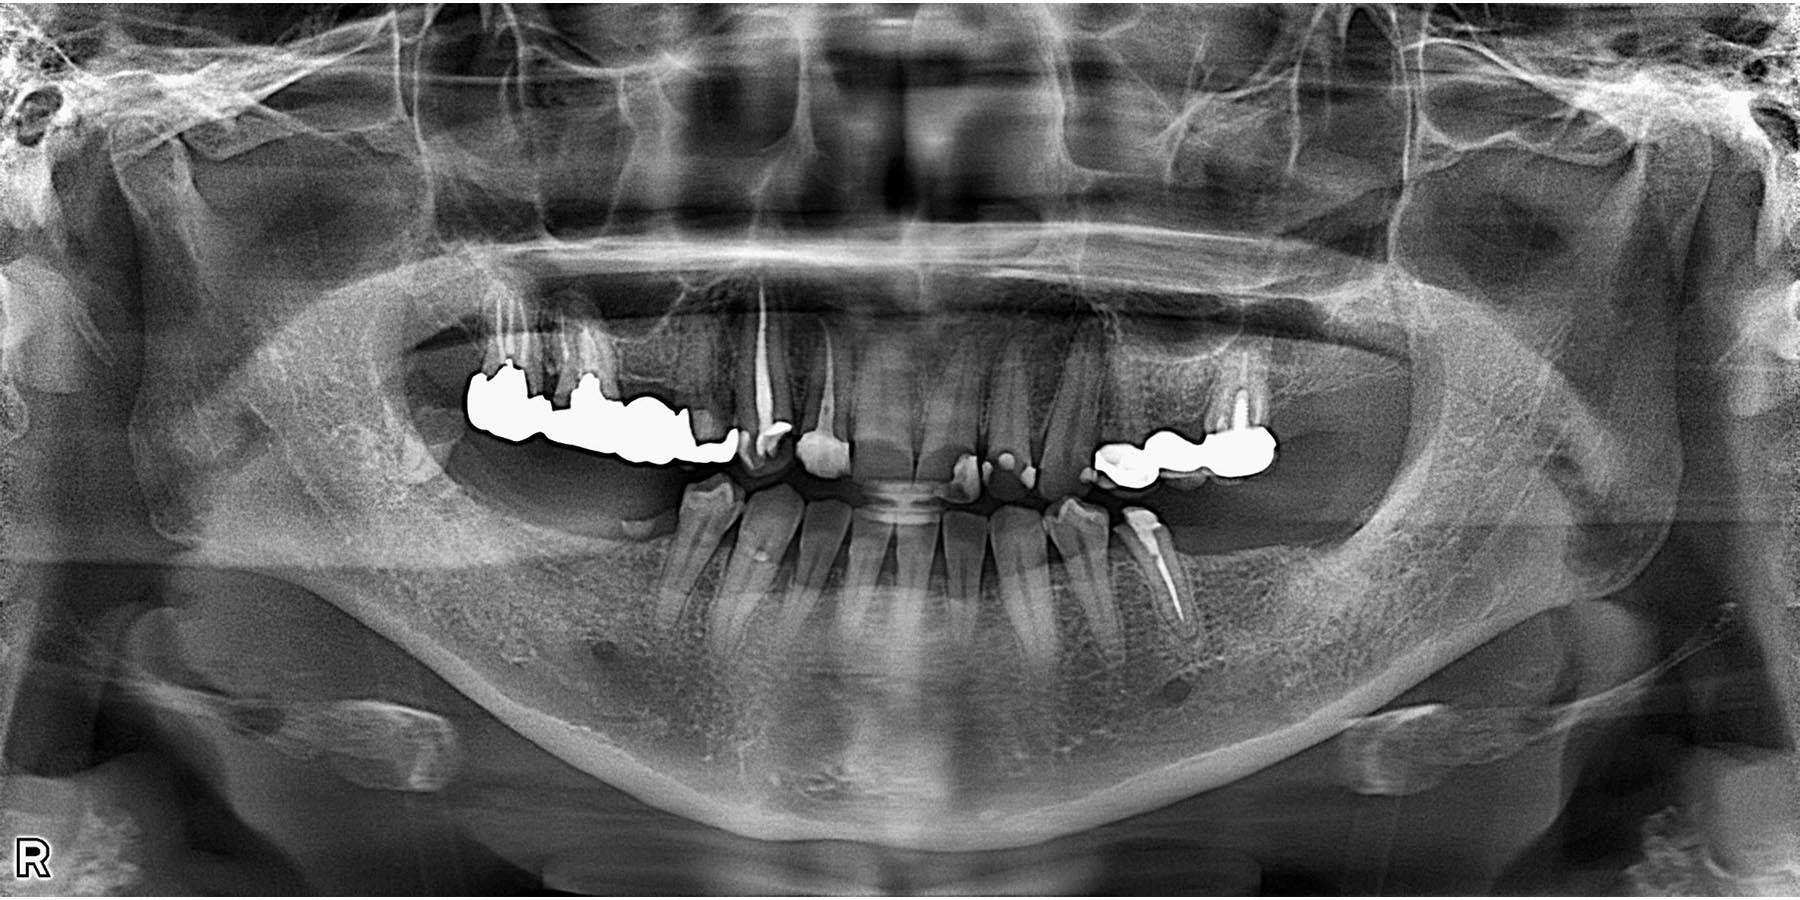

治療前

治療前(CT)

| 主訴 | 下顎のインプラント治療をしたい |

| 治療内容 | 左下5.7右下6のインプラント治療(3本) |